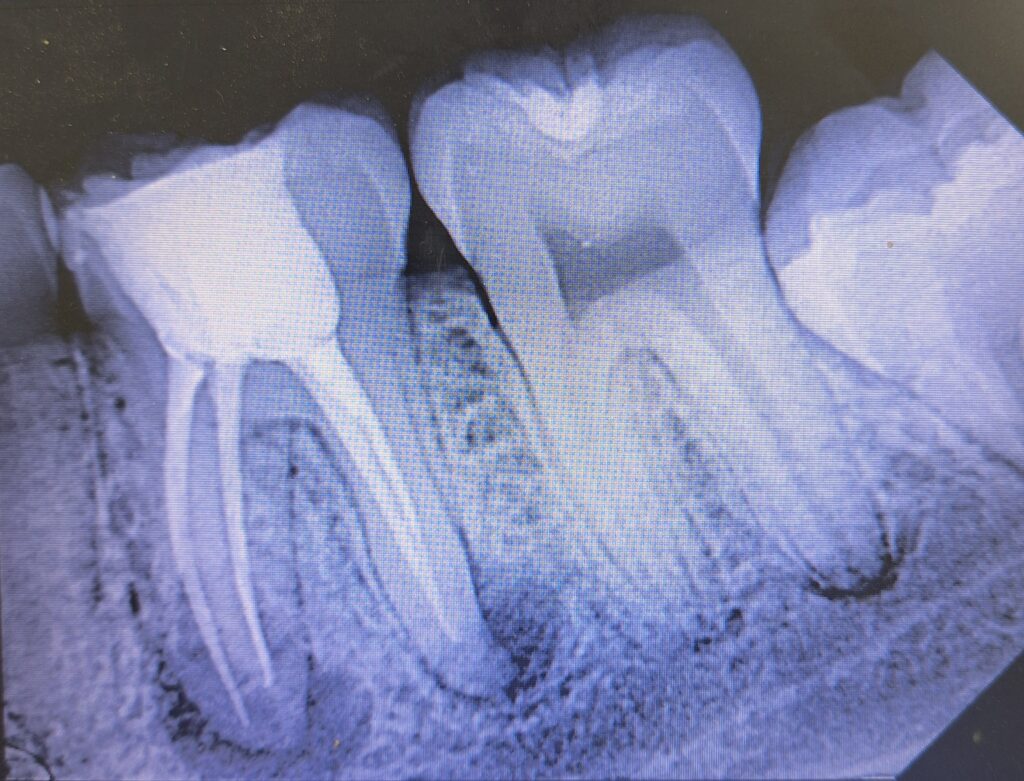

Veja alguns de meus casos